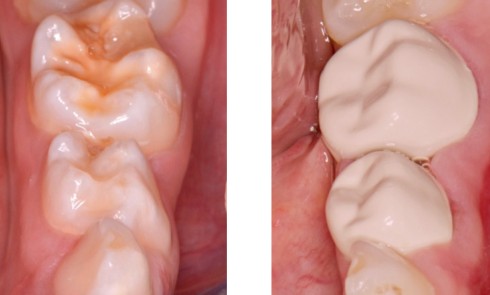

Dès l’atteinte d’une face de l’émail de la couronne dentaire, un traitement doit être proposé. Les traitements généralement conservateurs seront gradués selon la sévérité et l’activité de la lésion carieuse (fig. 1).

- L’évolution de la maladie carieuse : cette pathologie bactérienne, multifactorielle, se transmet très vite d’une dent à une autre dans la cavité orale de l’enfant. Ainsi, avant l’âge de 6 ans, la carie précoce de l’enfant (CPE) peut atteindre un stade sévère et ne plus permettre à l’enfant de mastiquer sans douleur (fig. 2).